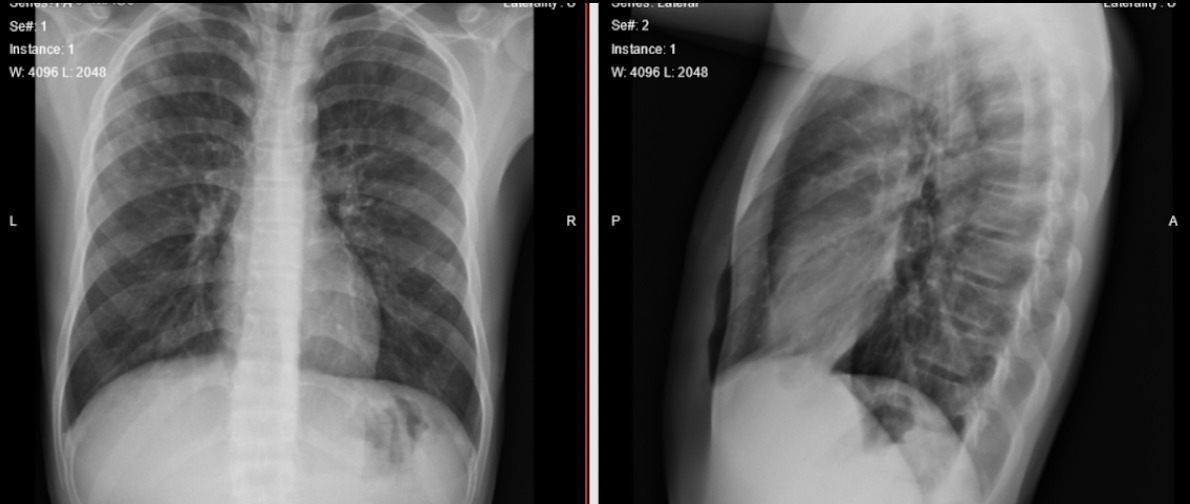

Dado el cuadro respiratorio agudo y signos de dificultad respiratoria, se decidió iniciar manejo con oxígeno suplementario a bajo flujo con una fracción inspirada de oxigena aproximada del 24 %, los gases arteriales presentaron: pH =7.46; pCO2 = 26.4 mm Hg, PO2 = 53 mm Hg, HCO3 19.1 mEq/l; base exceso (BE) = -5 mEq/L, lactato en 1.72 mmol/L, con relación entre la presión arterial de oxígeno y la fracción inspirada de oxígeno (PAFI) de 220. Teniendo en cuenta la altura a la que se encuentra el municipio de Chiquinquirá se consideró una hipoxemia no respondiente a terapéutica, con trastorno de la oxigenación leve asociada a trastorno ácido base tipo alcalemia respiratoria con hiperlactatemia. El gradiente alveolo capilar se encontraba aumentado para lo esperado. En la radiografía de tórax de ingreso se evidenciaron múltiples infiltrados generalizados con opacidades algodonosas diseminadas en ambos campos pulmonares sugestivas de edema pulmonar (Ver figura 1). No se encontraron signos de derrame pleural ni de patologías asociadas.

Figura 1. Exploración radiológica inicial.